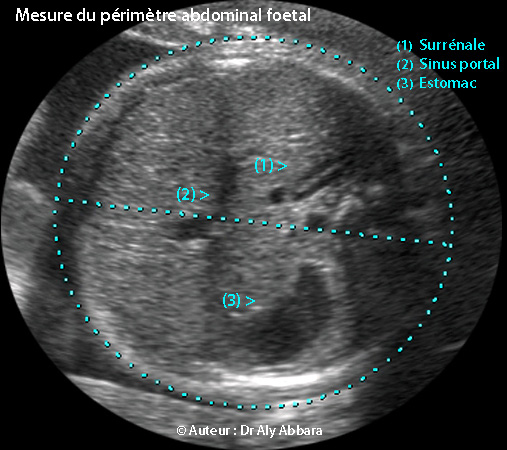

Coupe de mesure du périmètre abdominal (PA) et et du diamètre abdominal transverse (DAT)

Coupe et technique de la mesure du DAT (diamètre abdominal transverse)

et du PA (périmètre abdominal)